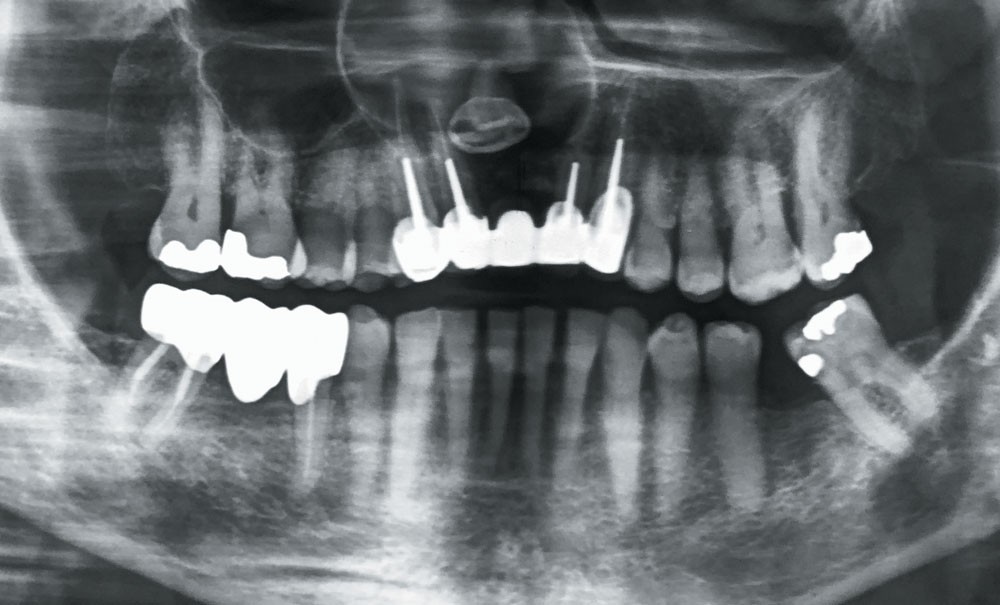

2. Le diagnostic de lésion kystique maxillaire étant posé, un examen tomodensitométrique est réalisé. Il met en évidence un volumineux kyste maxillaire antéro latéral droit (fig. 2 et 3).

Il existe :

a. une dent incluse

b. une lyse du plancher de la fosse nasale droite

c. une extension vers le sinus maxillaire droit

d. une lyse osseuse palatine